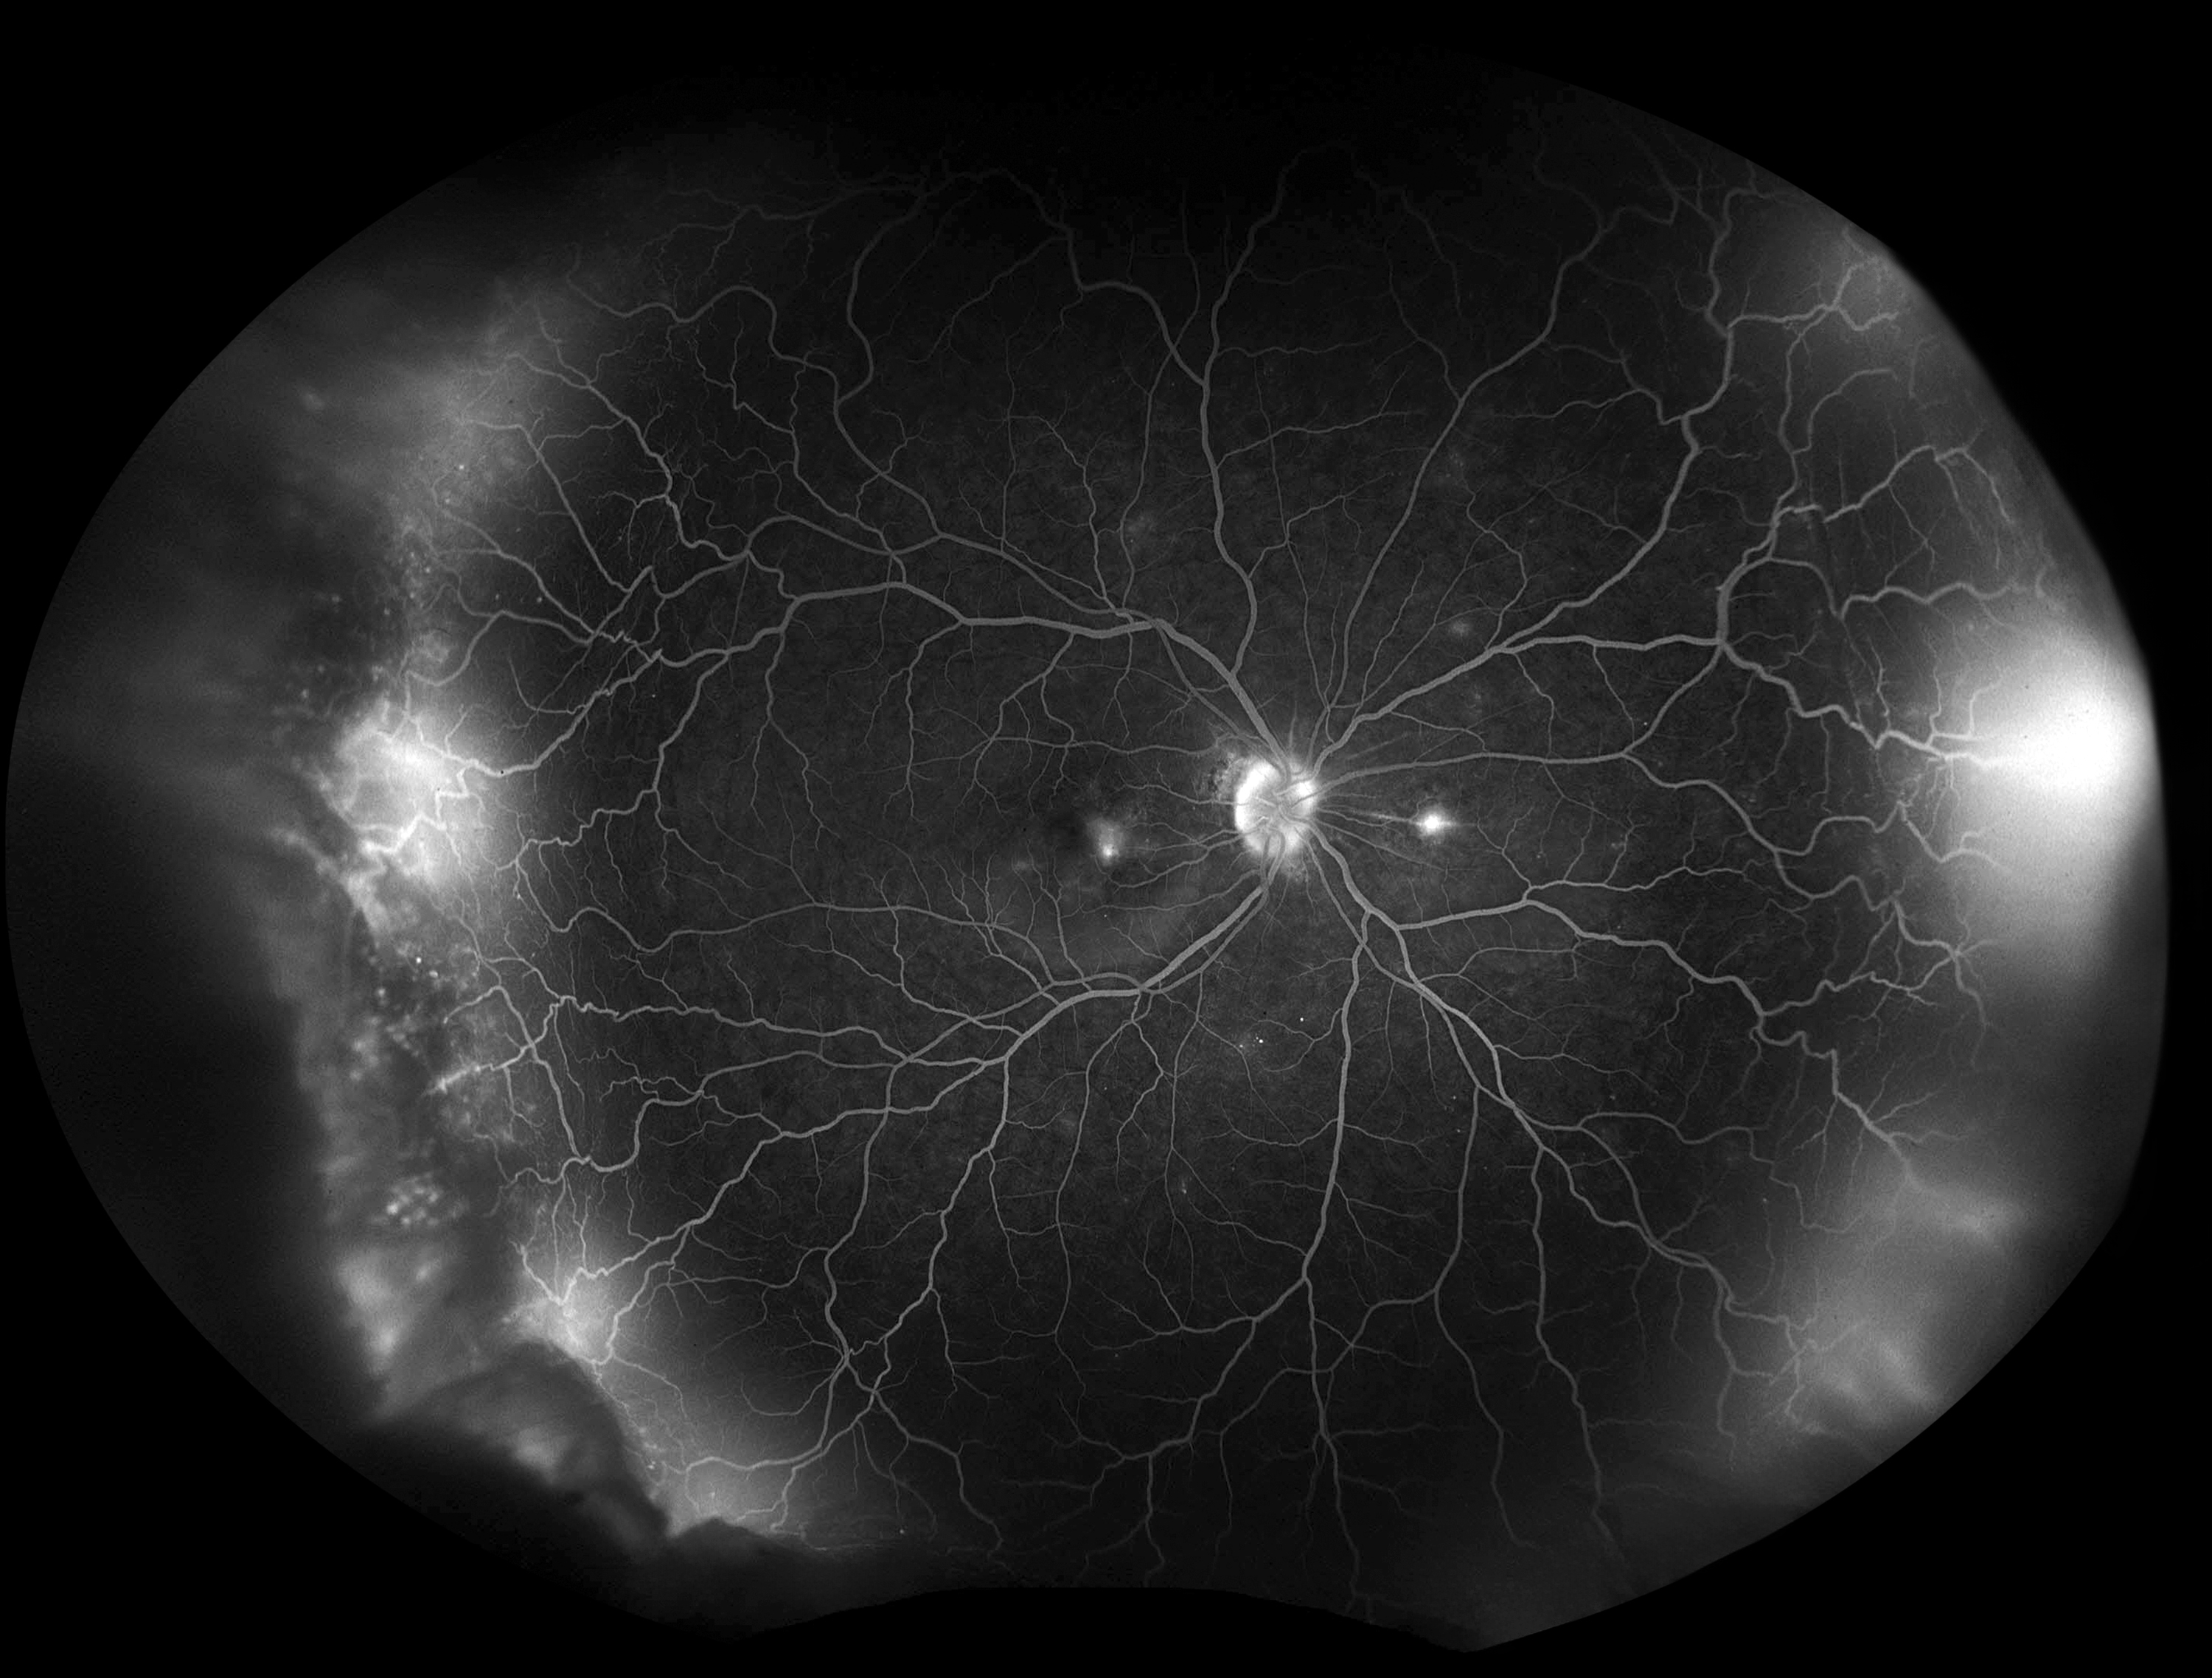

Uveitis Presented by Megan Allis, CRA, OCT-C This photograph received Third Place, Fluorescein Angiography (UWF) in the 2025 OPS Scientific Exhibit. Filed Under Cornea OPS Photo